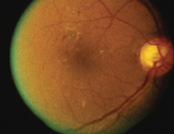

![]() 正常视网膜 |

糖尿上眼早期并没有症状,眼睛不红不痛,视力亦正常。然而,若病情没有受到控制,视网膜上的微丝血管会逐渐膨胀,出现微小血管瘤,渗漏出血清和血脂,部份微丝血管更会闭塞并导致缺氧。如果病情不受控制,或患者根本不知道自己糖尿上眼,眼睛会长出新生血管,它们相当脆弱,很容易突然爆裂,导致血块渗入眼球中的玻璃体。患者的眼睛会因此出现大量飞蚊,随後视力会下降,严重者甚至突然完全失明。